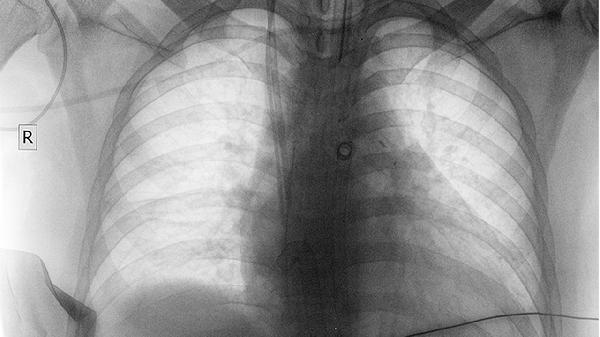

2.传统检查存在局限性

常规胸片对微小病灶识别度有限,就像隔着毛玻璃看风景。而低剂量螺旋CT能清晰显示毫米级结节,这种检测方式辐射量仅相当于乘坐两小时飞机。